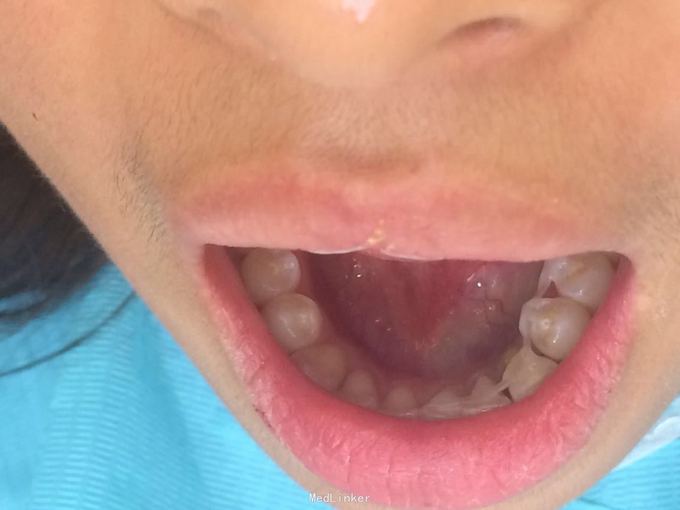

牙脱位24小时要求处理 昨晚8点吃铁板烧的时候咬到硬物致左下尖牙脱落到铁板烧中污染,取出牙齿用纸巾保存,第二天到就近医院处理,医生建议其做种植牙修复或烤瓷桥修复,脱落牙齿无法保留,患者又陆续问了4家医院都无法保留脱落牙齿,晚上8点找到我院(夜班8点下班)要求处理。

D3完全脱位,伤口血凝块已经凝固,颊侧牙龈钝性撕裂。D2D4无叩痛和松动。脱落牙齿牙体硬组织完好,牙周膜干裂,牙体上有纸屑和食物残渣,根尖有牙髓组织呈黑红色。